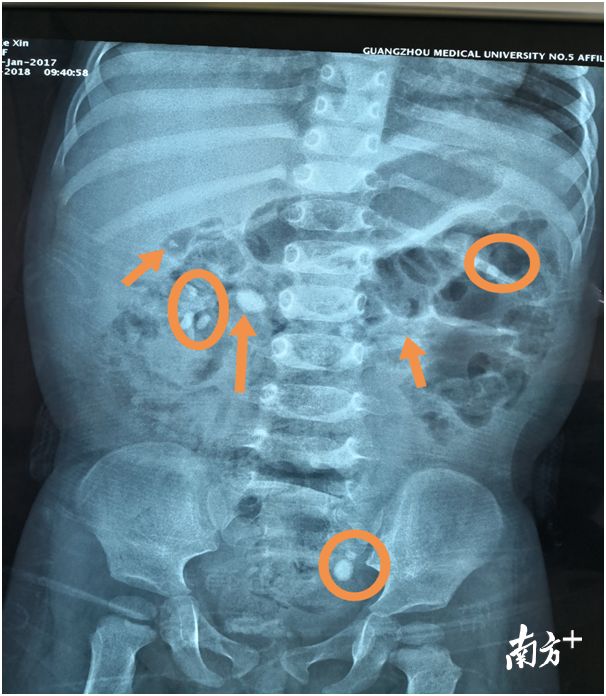

- 一岁女童双肾长满结石 只因家长做错这件事

- 快速找到小新推送的文章,请设“置顶”哦~ 点击上方“新快报” → 点击右上角“...” → 点选“设为星标 ★ ” 活泼可爱的小钟(化名)家在梅州偏远农村,才1岁10个月大。偶然一次,妈妈抱她尿尿的